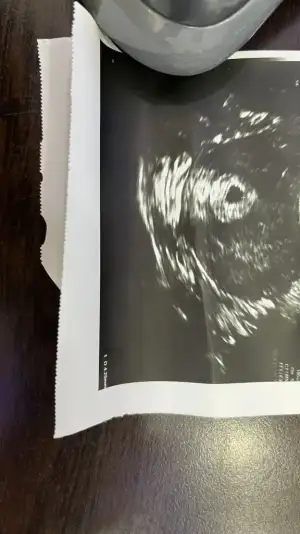

Kızlar merhaba sag tarafımda sancı ile uyandım kendi doktorum sehir dısında oldugu için baska bir doktordan randevu alıp gittim transfere göre 4+5 son adete göre 4+2 haftalık görünüyorum doktor baktı keseye burda normal dedi agrıların olabilir dedi ve gönderdi yolk kesesi falan hiç bişe demedi kese boyutunuda demedi ultrason kagıdından anlayanlar bakabilir mi